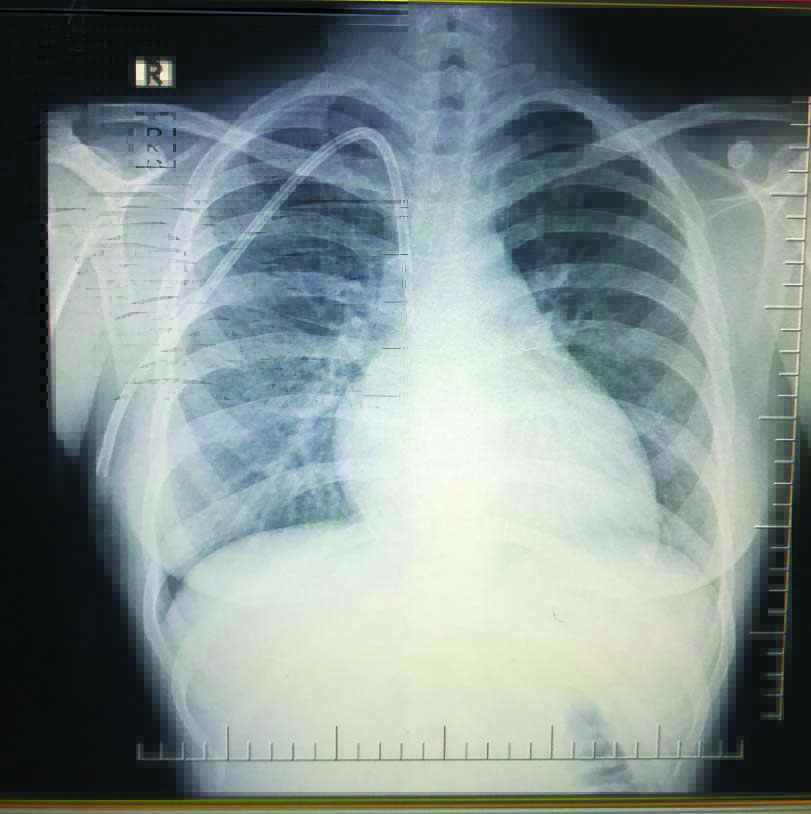

After achieving haemostasis and securing the catheter, sterile dressing was applied. Chest X-ray to confirm tip position [Table/Fig-1] was performed in all patients prior to initiation of haemodialysis. Catheters were handled by dialysis technicians and staff with sterile precautions. Catheter insertion complications like pneumothorax, haemothorax, pericatheter bleed, if any were noted. Subsequently follow-up data regarding catheter flow rates, incidence of CRBSI, catheter longevity were noted.

Chest X-ray depicting TCC and position of catheter tip at junction of Superior Vena Cava (SVC) and right atrium.